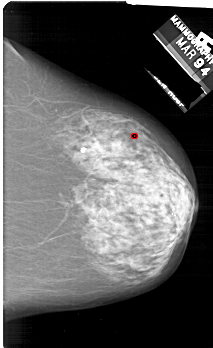

A_1829_1.LEFT_MLO

LEFT_MLO LINES 6676 PIXELS_PER_LINE 4171 BITS_PER_PIXEL 12 RESOLUTION 43.5 NON_OVERLAY